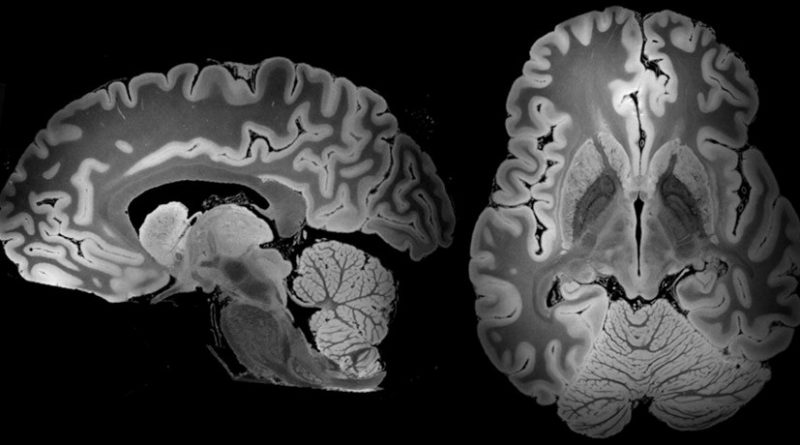

Read MoreUna resonancia magnética de 100 horas ha capturado el más alto nivel de detalle conseguido hasta ahora un cerebro humano al completo